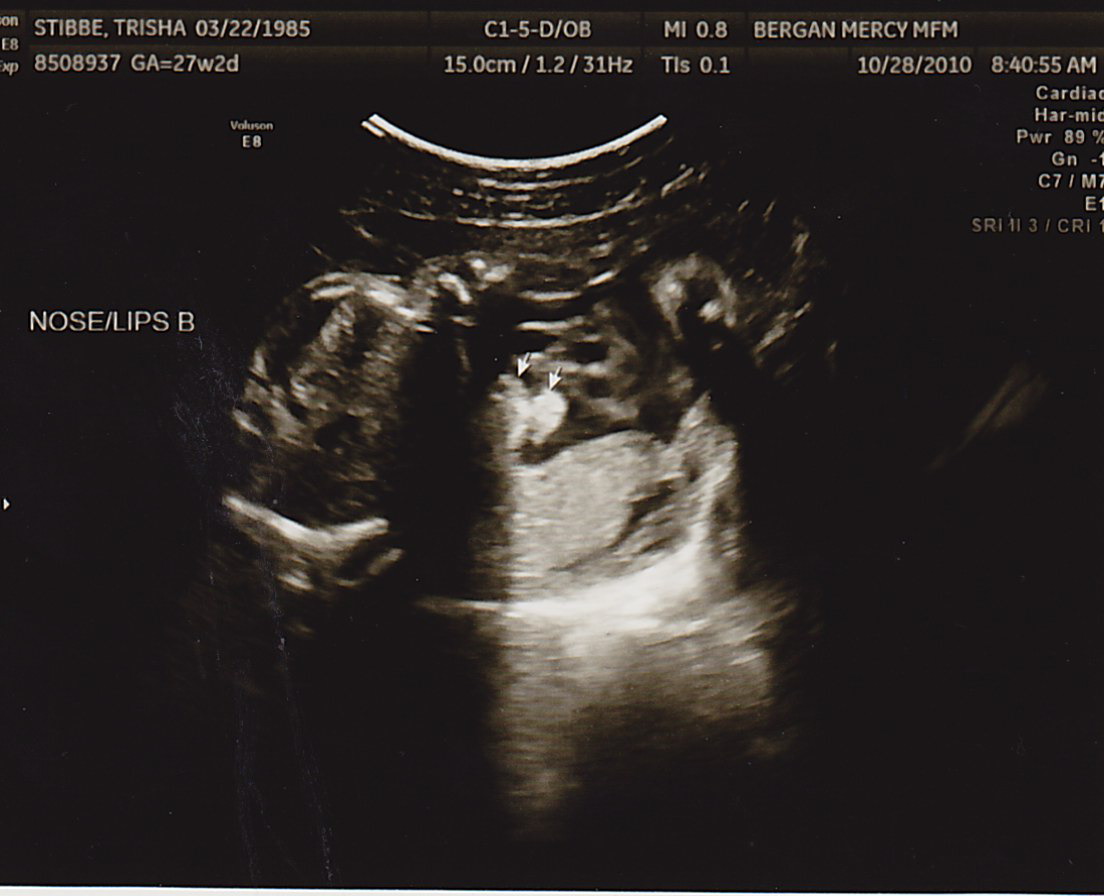

The little guys just haven’t been photogenic lately, but here’s a few pictures…